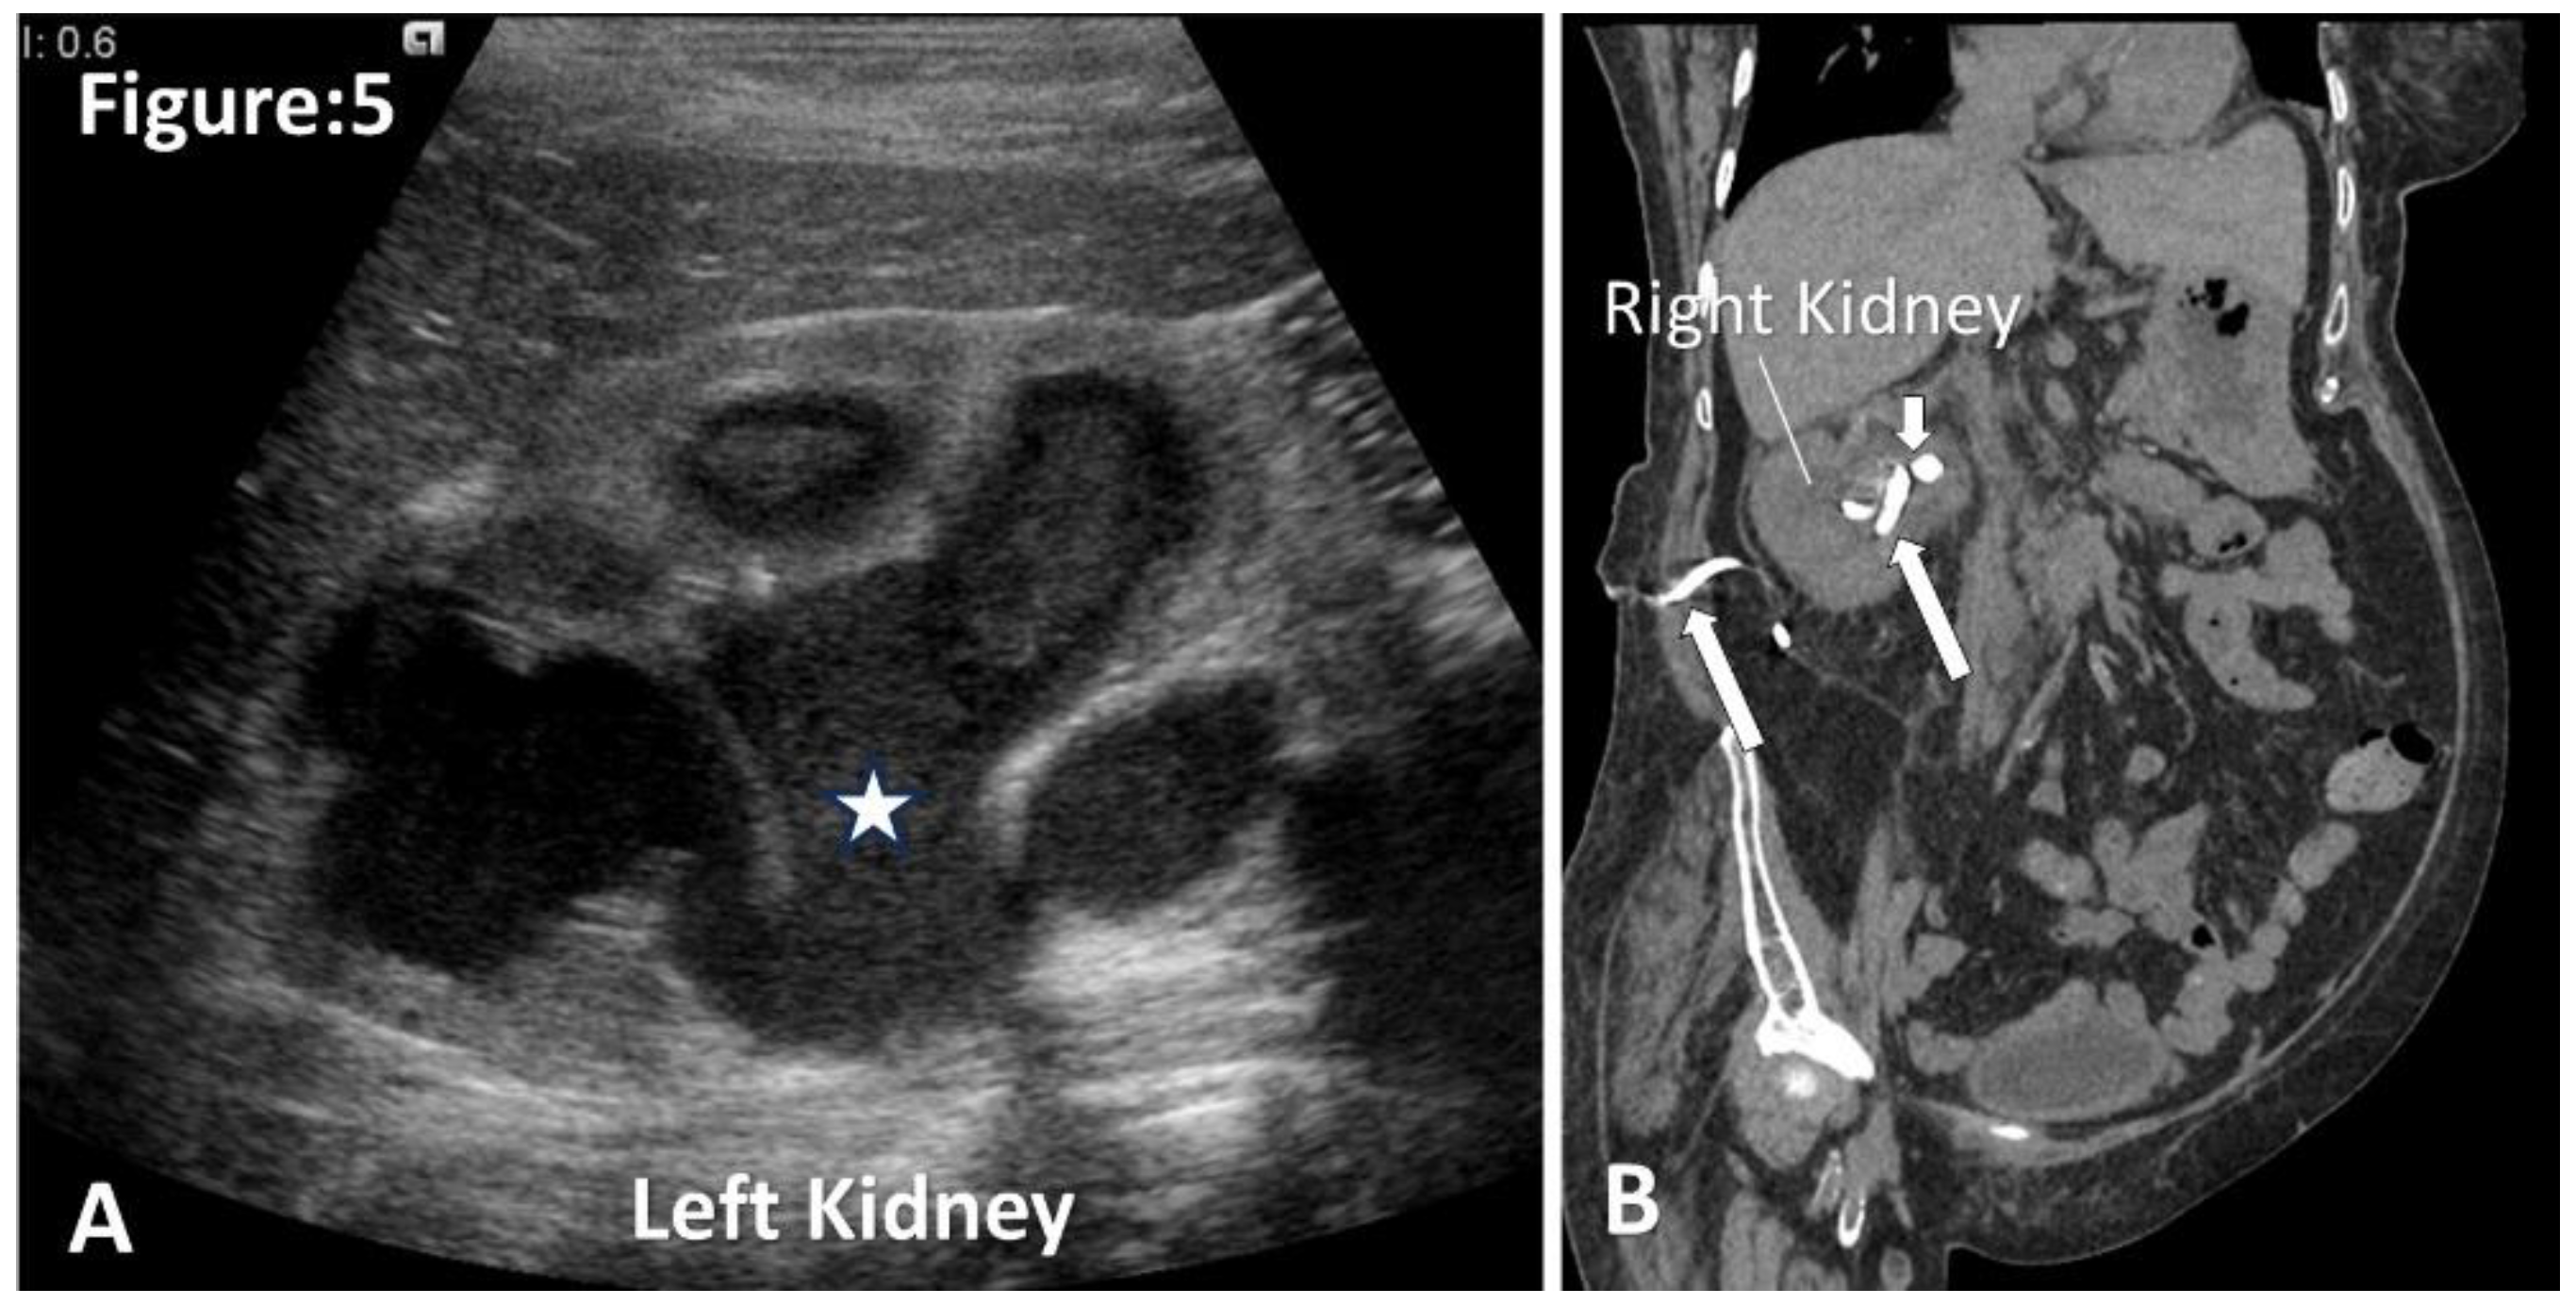

Pyonephrosis